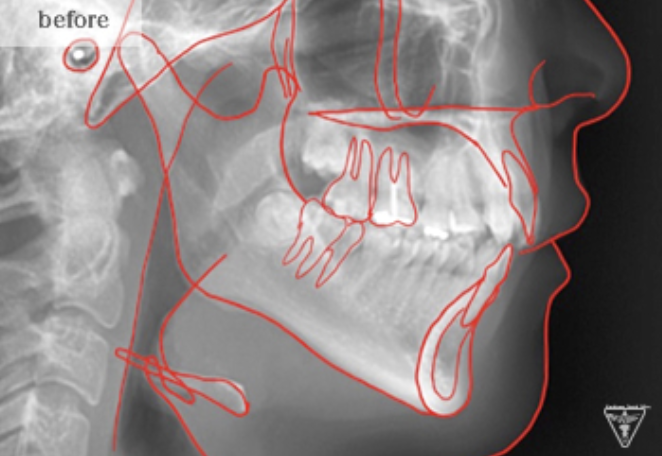

治療前

治療後